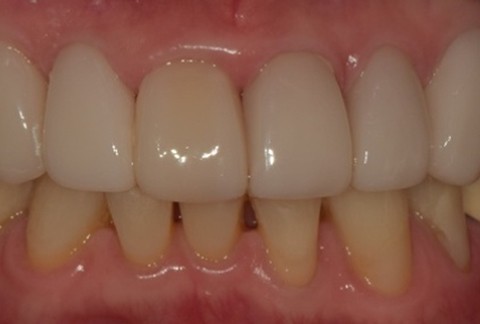

임플란트-전후사진